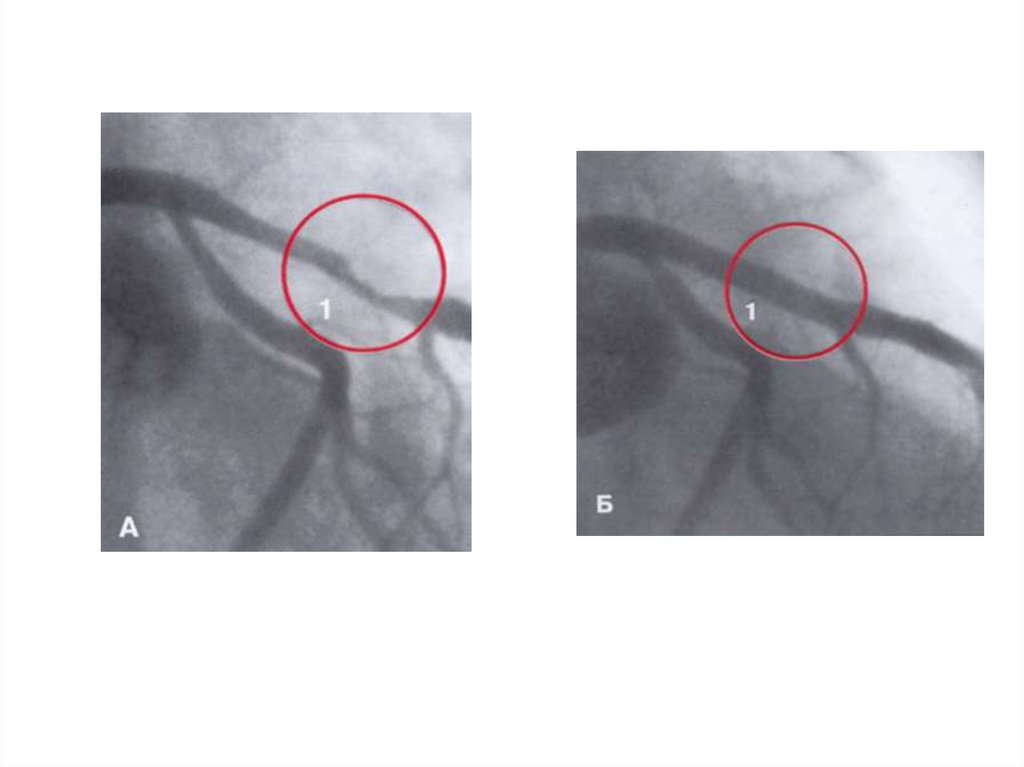

Множественные стенозы левой коронарной артерии